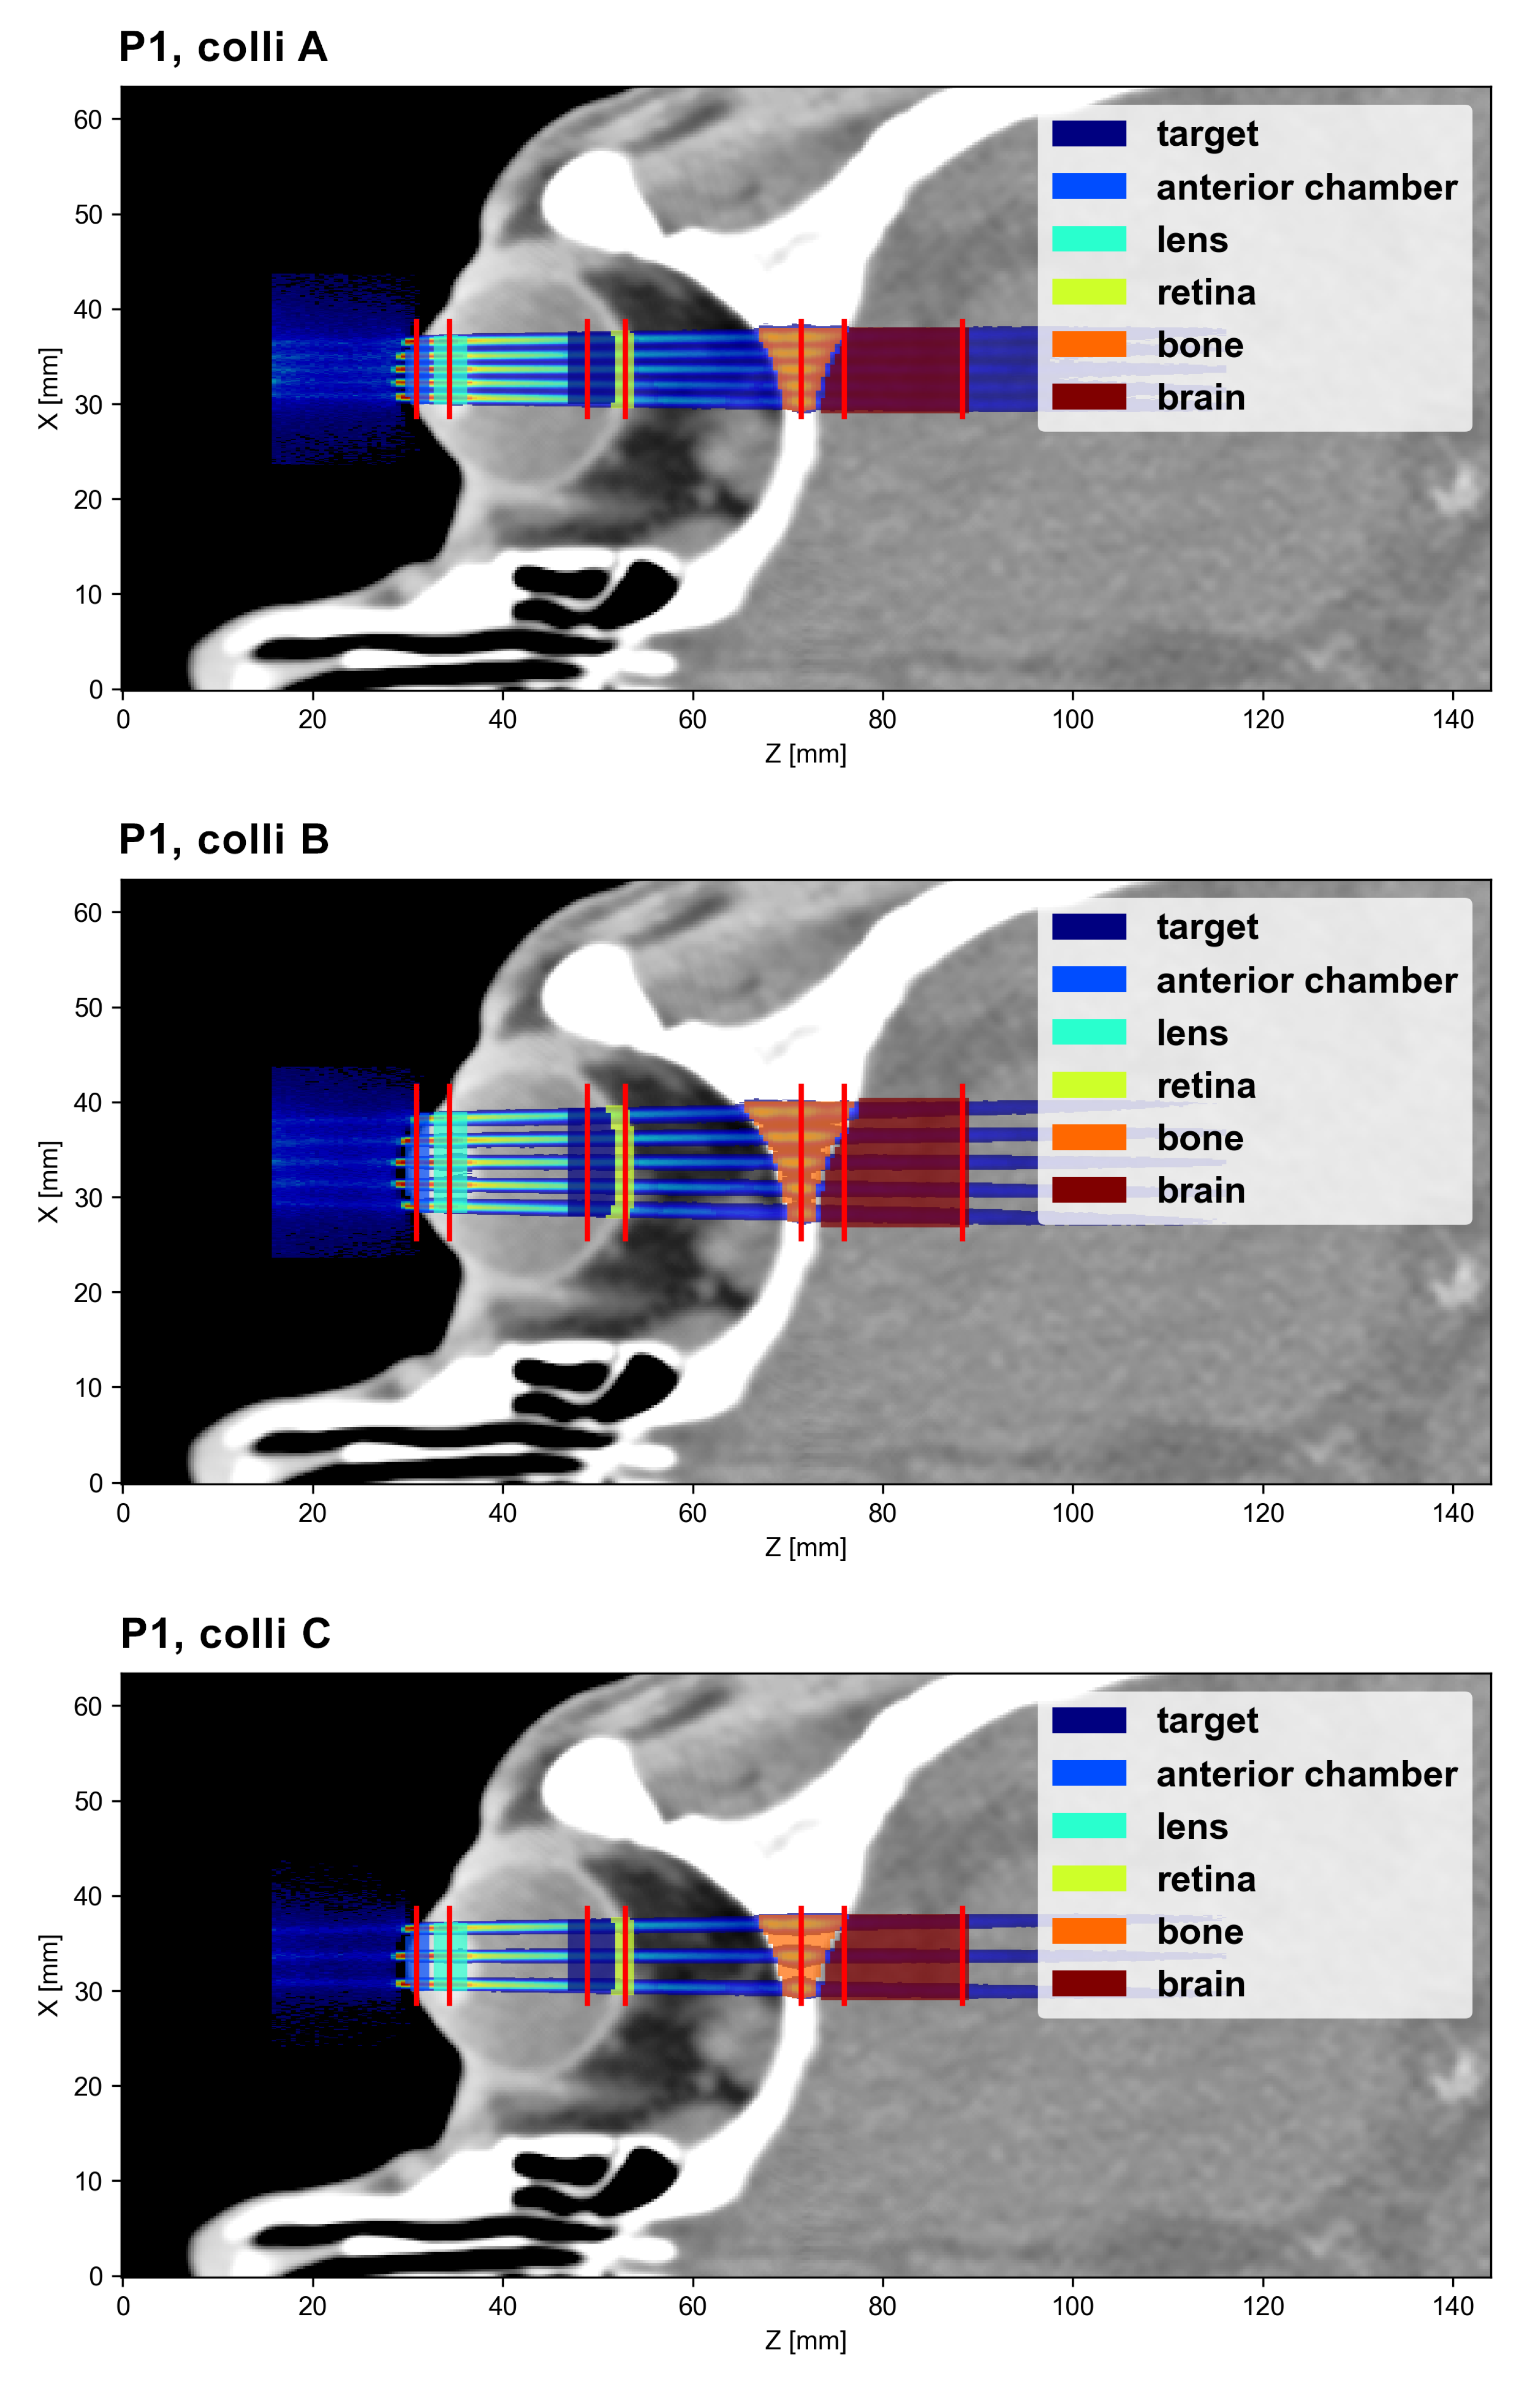

2.1. Irradiation Configurations

| Label | No. of Slits | Slit Height [mm] | Slit Width [m] | Divergence Angle [deg] | Spacing at Exit [m] | ||||

|---|---|---|---|---|---|---|---|---|---|

| colli A | 5 | 10 | 400 | 400 | 425 | 0.595 | 0.632 | 1150 | 1275 |

| colli Ah | 5 | 5 | 400 | 400 | 425 | 0.595 | 0.632 | 1150 | 1275 |

| colli A3s | 3 | 10 | 400 | 400 | - | 0.595 | - | 1150 | - |

| colli B | 5 | 10 | 400 | 409 | 500 | 0.611 | 0.744 | 1900 | 1875 |

| colli C | 3 | 10 | 400 | 425 | - | 0.632 | - | 2425 | - |

| Position | Depth [cm] | FWHM/ctc [mm] | ||

|---|---|---|---|---|

| Colli A | Colli B | Colli C | ||

| Surface | 0 | 0.69/1.3 | 0.64/2.2 | 0.64/2.9 |

| Target | 2 | 0.90/1.5 | 0.86/2.4 | 0.85/3.1 |